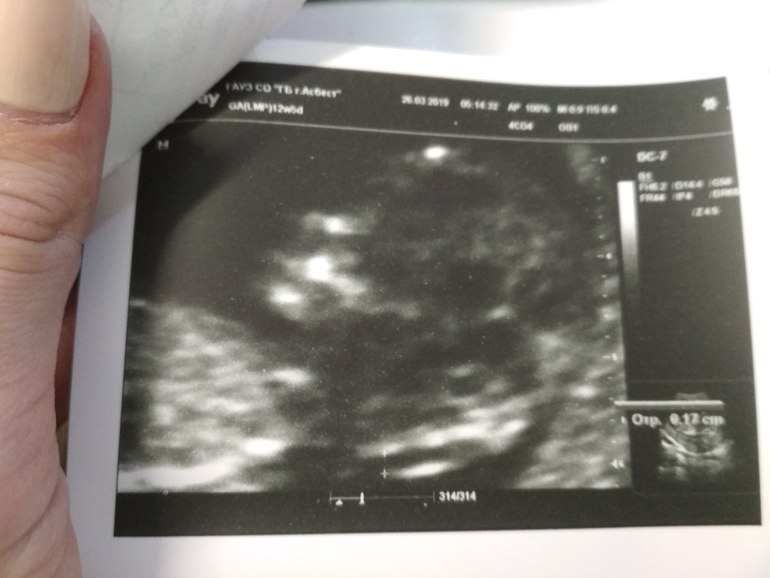

На первом скрининге была. Все хорошо. Повидались,ручкой помахали. Срок был 12+5. ЧСС 161,ростик 64 мм. Предположили парня. Врач особо делала акцент на слове "предположили". Ну,у меня пока никаких предчувствий и собственных предположений на этот счет нет. Подождем следующего УЗИ. Фото на память